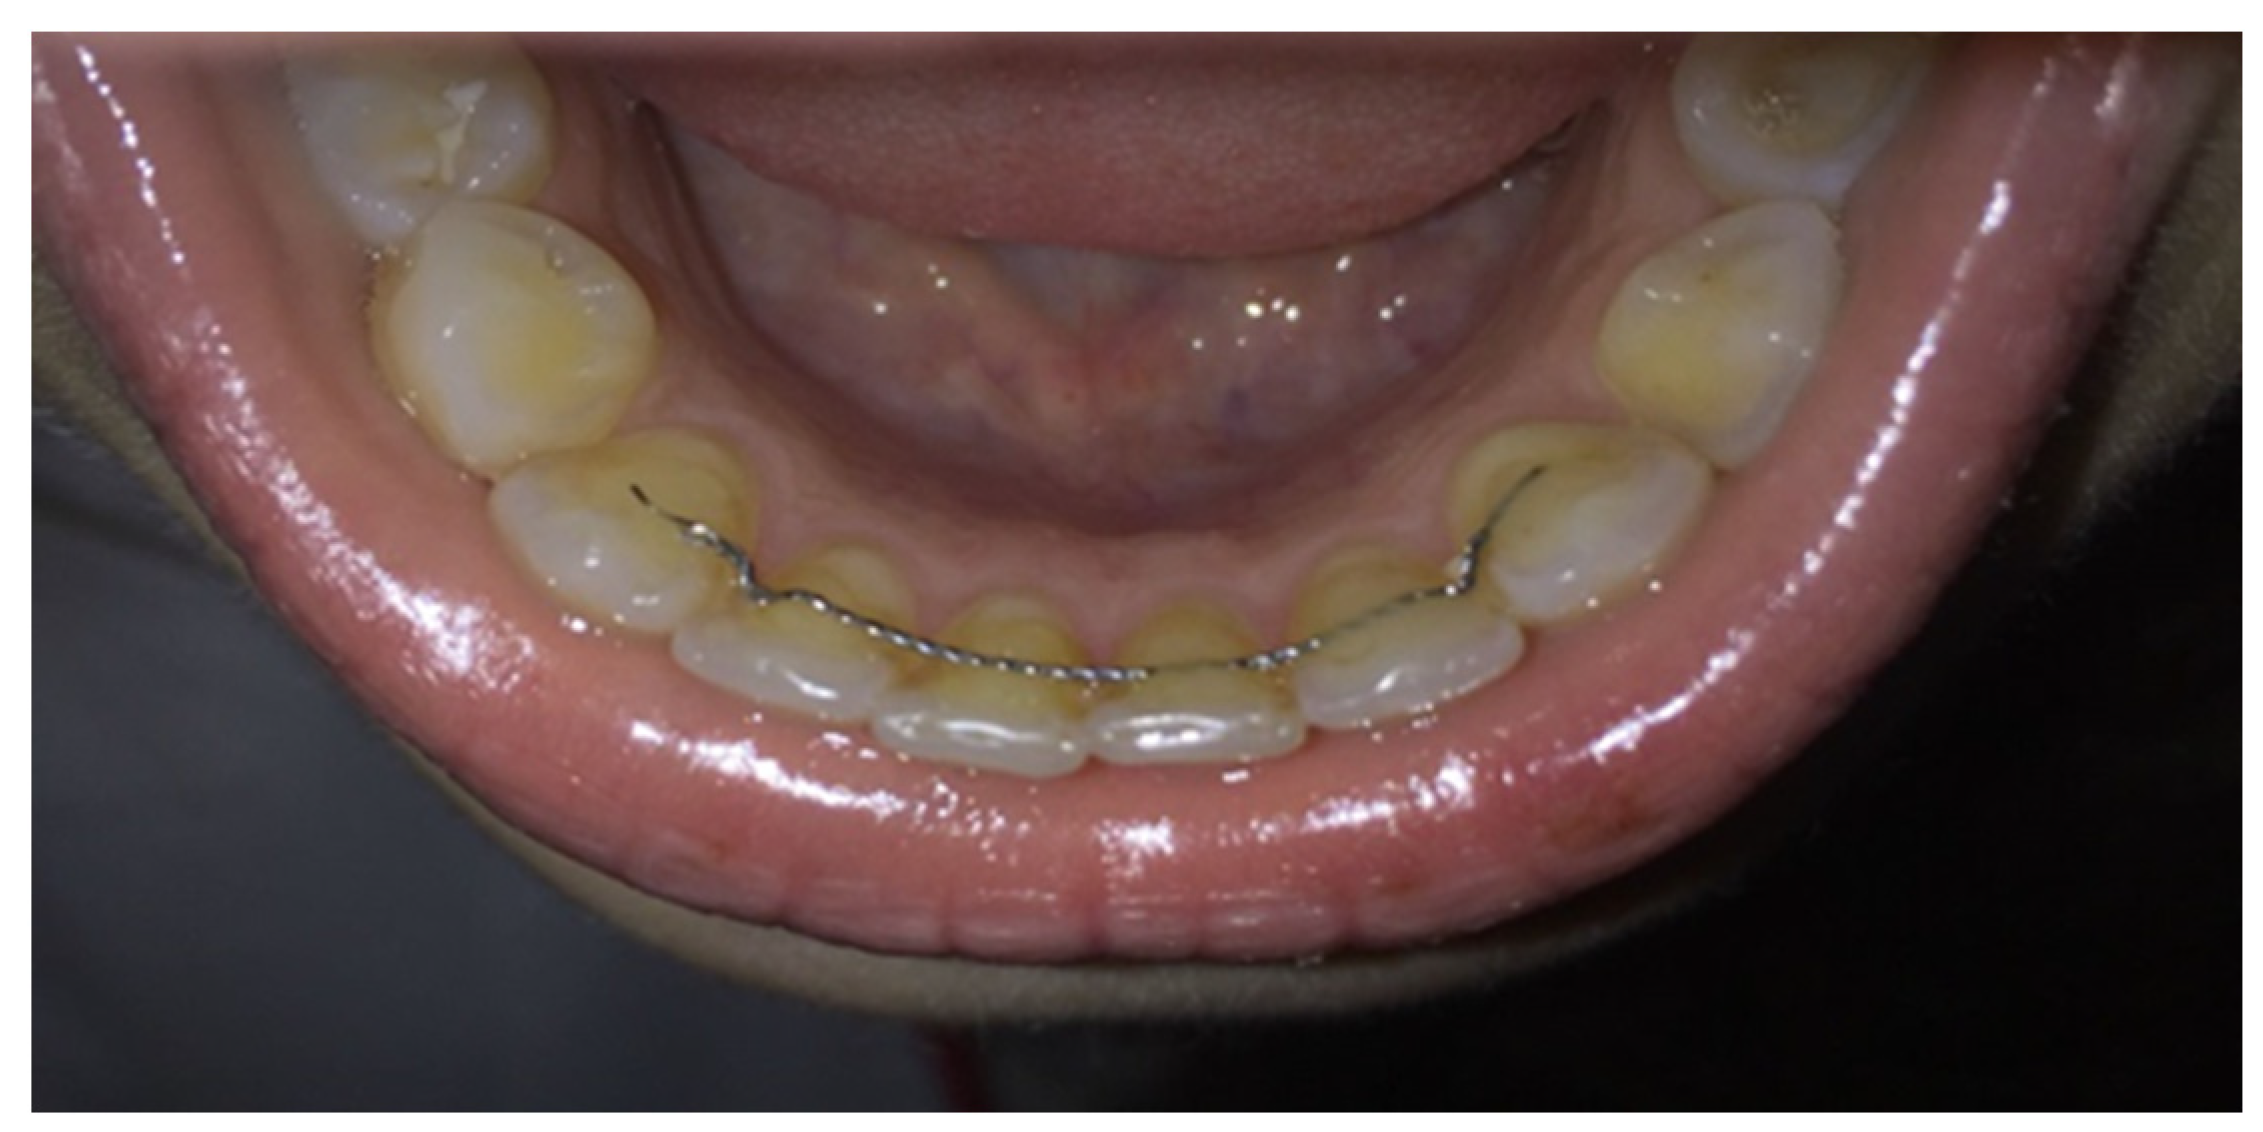

Fixed retainers (Figure 3) were introduced into clinical practice in the 1970s to prevent recurrences in the lower inter-canine zone are now commonly used [8,12]. Their advantages are aesthetics, effectiveness, the long-lasting, and the character of being fixed by which their behavior does not depend on the patient’s cooperation. The disadvantages are fragility, the vulnerable bonding technique, and the possibility of causing periodontal pathology due to a more difficult oral hygiene [8,12].

Figure 3. Inferior fixed retainer used in the study.